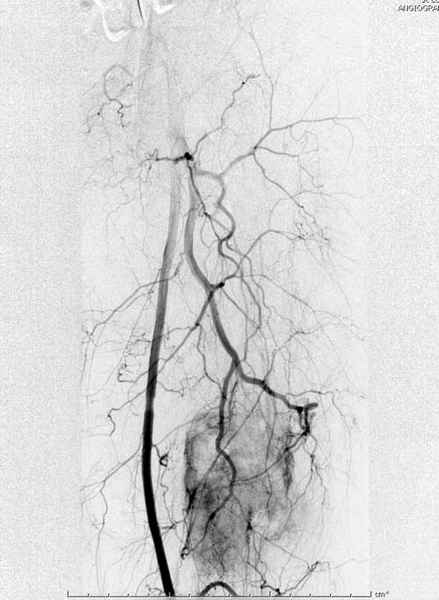

Для предупреждения кровотечения во время рассверливания, за день до операции провели эмболизацию сосудов питающий метастаз. http://radiology.rsnajnls.org/cgi/reprint/150/3/673.pdf (7-11, 12-15-16)

С минимальным рассверливанием и ретроградным методом провели остеосинтез бедра 12 мм гвоздем. (17-20)

Кровопотеря во время операции меньше 100 мл.